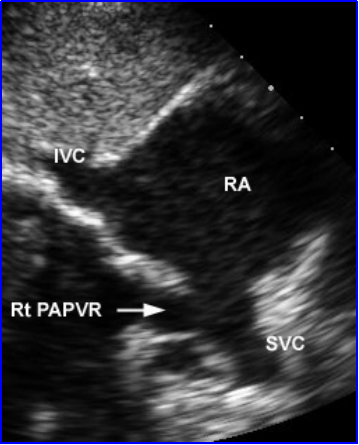

房间隔缺损:超声心动图表现

房间隔缺损(上腔型)合并右上肺静脉异位引流

(间接征象)